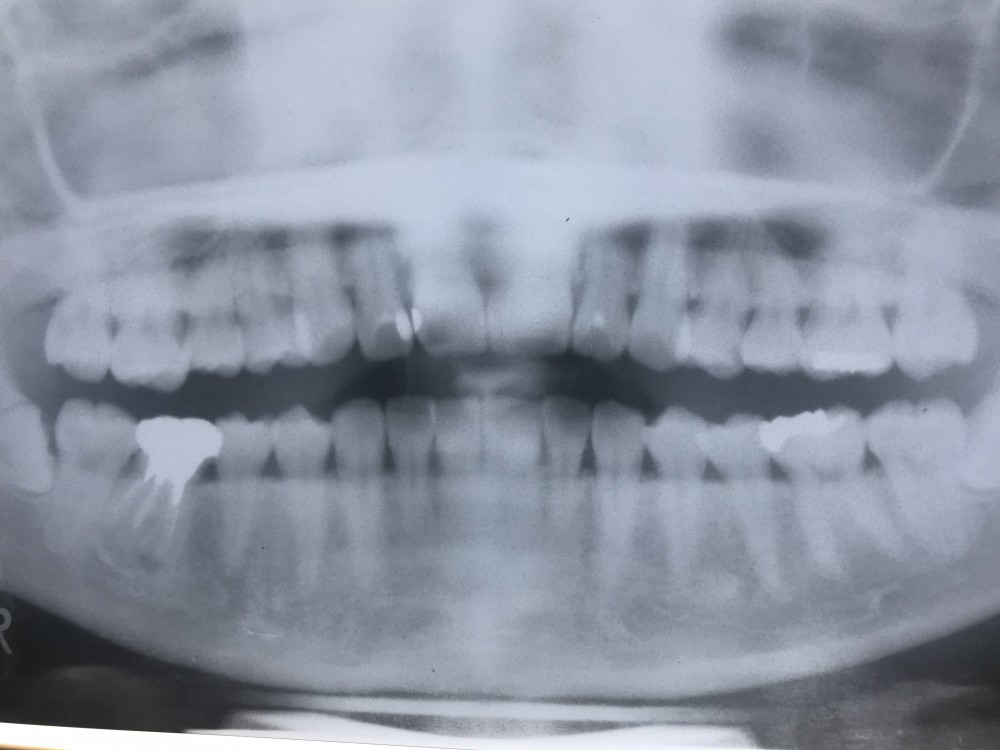

下の画像は初診時より9年4ヶ月後 のもの。

30歳0ヶ月

症状なし

近心根尖に骨吸収見られるのは治癒過程との判断で良いと思います。